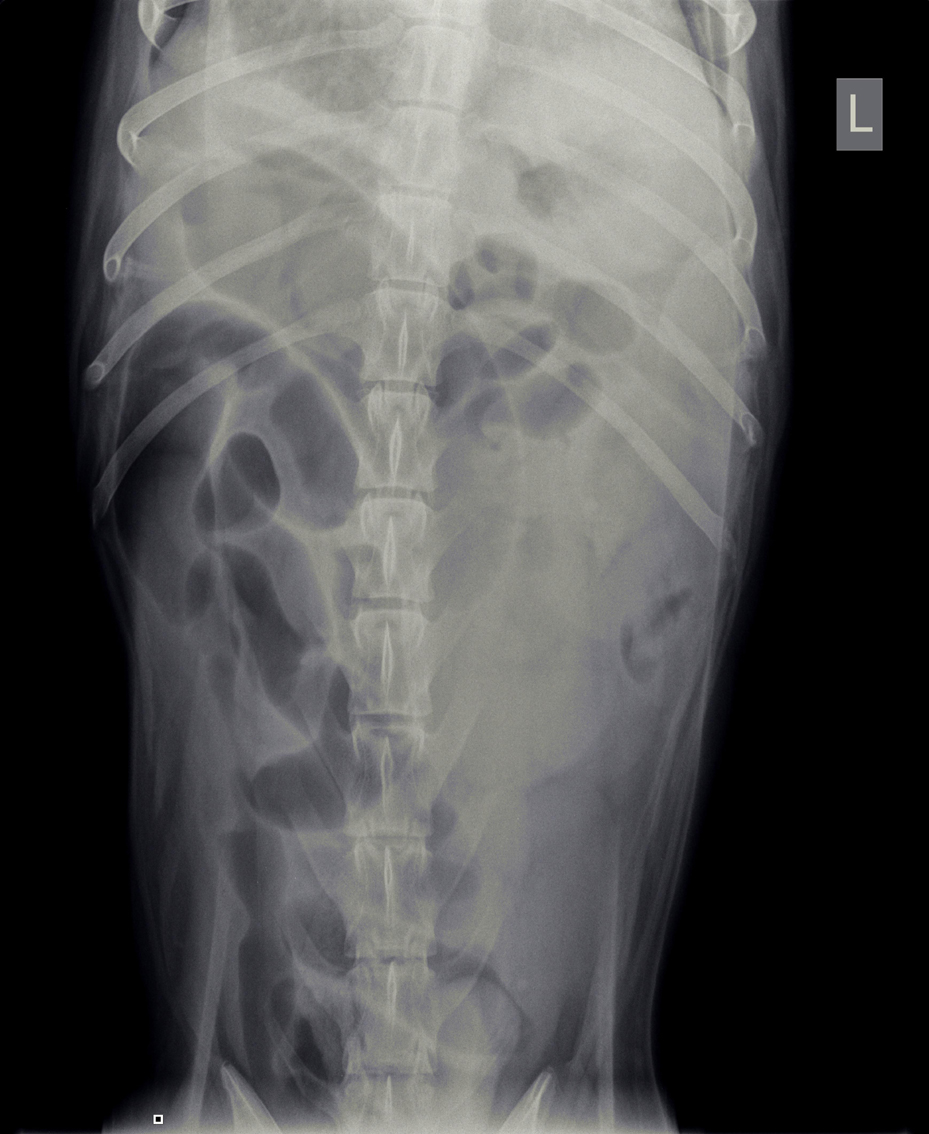

Op het spreekuur kwam T-Bone, een Duitse Herder reu van 1 jaar oud uit Tiel, die sinds een week wat slechter at, af en toe wat braakte en diarree vertoonde. Ondanks medicatie tegen overgeven bleef hij braken en na een paar dagen had hij geen ontlasting meer, alleen wat brij. Dit was reden om opnieuw naar de dierenarts te gaan. De röntgenfoto’s, die gemaakt werden, lieten veel lucht in het maagdarmkanaal zien. Dit kan onder andere wijzen op een verstopping.

Omdat de hond verder niet ziek was en de buik niet gevoelig, werd besloten om de röntgenfoto’s na een dag te herhalen. Hierop was er geheel geen verbetering zichtbaar in de buik ten opzichte van de dag ervoor.

De hoeveelheid lucht had zich zelfs vermeerderd, wat meer in de richting van een verstopping wees, mogelijk door een vreemd voorwerp. De eigenaren vertelden dat er een latex koetje vermist werd. Helaas is latex meestal niet zichtbaar op een röntgenfoto. De enige mogelijkheid om een verstopping te verhelpen die niet reageert op medicatie, is opereren, dus diezelfde middag werd T-Bone voorbereid voor operatie.